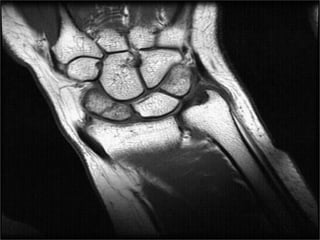

MRI

T1-weighted images obtained in a single plane (coronal) are

typically sufficient to determine the presence of a scaphoid

fracture.

Gaebler prospectively performed MRI on 32 patients, at

average of 2.8 days post injury

– 100% sensitivity and specificity

In recent study Dorsay has shown that immediate MRI

provides cost benefit when compared to splintage and repeat

x-ray

• Determine preop vascularity in a diagnosed scaphoid

• Acute fractures- Normal or decreased T1 intensity or

increased T2 intensity.

• Low T1 and T2 marrow signal intensity indicates poor

vascularity.